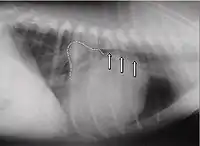

Les signes les plus fréquents d'une capacité cardiaque diminuée sont : la diminution des performances, la toux, les troubles nocturnes et la dyspnée. À l'auscultation, on[Qui ?] peut entendre dans la plupart des cas des bruits cardiaques holosystoliques d'intensité constante, de force des plus variables (degrés 1 à 6). Le bruit maximum de la valve mitrale (punctum maximum) est chez le chien dans le 5e espace intercostal, au niveau de la pointe du cœur. À la radio, un cœur dilaté peut être constaté. L'atrium gauche peut alors revêtir la forme d'un triangle (« triangle mitral ») décalé en direction caudo-dorsale. L'angle usuel entre les bronches et la colonne vertébrale peut disparaître en un trajet parallèle, et même l'atrium peut comprimer les bronches et l'irritation mécanique augmente alors les symptômes de toux. Dans les cas avancés, un œdème pulmonaire est diagnostiqué. L'électrocardiogramme est en général peu spécifique, il y a en partie des suggestions d'atrium dilaté (onde P allongée, au-delà de 0,04 s) ou d'un ventricule dilaté (complexe QRS plus long que 0,06 s). En outre, il peut y avoir des extrasystoles auriculaires ou ventriculaires, parfois une fibrillation auriculaire. Ce symptôme est fréquent chez les chiens avec une insuffisance mitrale fonctionnelle due à une cardiomyopathie dilatative. À l'échocardiographie Doppler, il est facile de reconnaître une insuffisance mitrale. Les autres conséquences qui surviennent sont : un élargissement du ventricule en raison de la surcharge en volume, souvent une hypercontractibilité en raison de mécanismes de compensation, et une oreillette substantiellement agrandie.